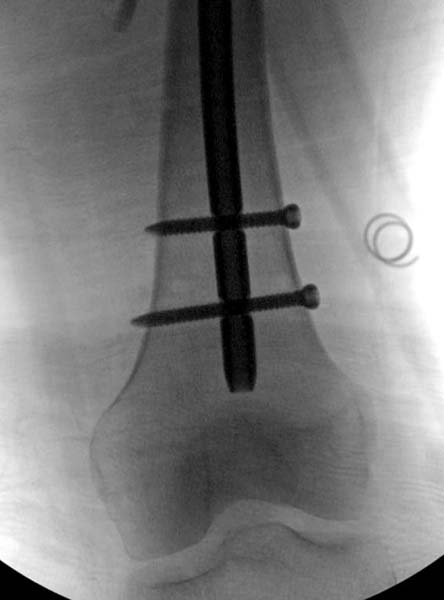

Остеосинтез бедра не стали делать из-за множественных переломов ребер с ушибом грудной клетки и поэтом у закончили фиксацию бедра наружным фиксатором.

Около 11.00 вечера больная переведена в реанимацию, без сознания, но стабильная.. На третьий день провели стабилизацию перелома бедра антеградным остеосинтезом.

Закрытый БИОС решает множественные проблемы связанные с лечением переломов, но проблема дистальной блокировки без рентгена до сих пор остается нерешенной. Рекламированные производителями приспособления для дистальной блокировки из-за различной кривизны кости не эффективны или стоит очень дорого (Smith&Nephew SureLock). Задержка операции из-за блокировки не всегда удовлетворяет, и многих вынуждает искать альтернативные методы фиксации. С результатами таких действий, остеомиелитом и несращениями, встречаемся в ежедневной жизни..

Для решения проблемы дистальной блокировки компания DigiMed недавно предложила систему блокировки без рентгена. Пока в стране только два набора и только для антеградных гвоздей, но компания работает над созданием устроиства для других гвоздей тоже..

Результат первых случаев показала отсутствие разницы между занятиями на муляжах, а также Workshop и с удивительной точностью вывел латерально над кожей специальное сверло. Дальше по сверлу тонкий направитель и проводится сверление каннюлированным сверлом....